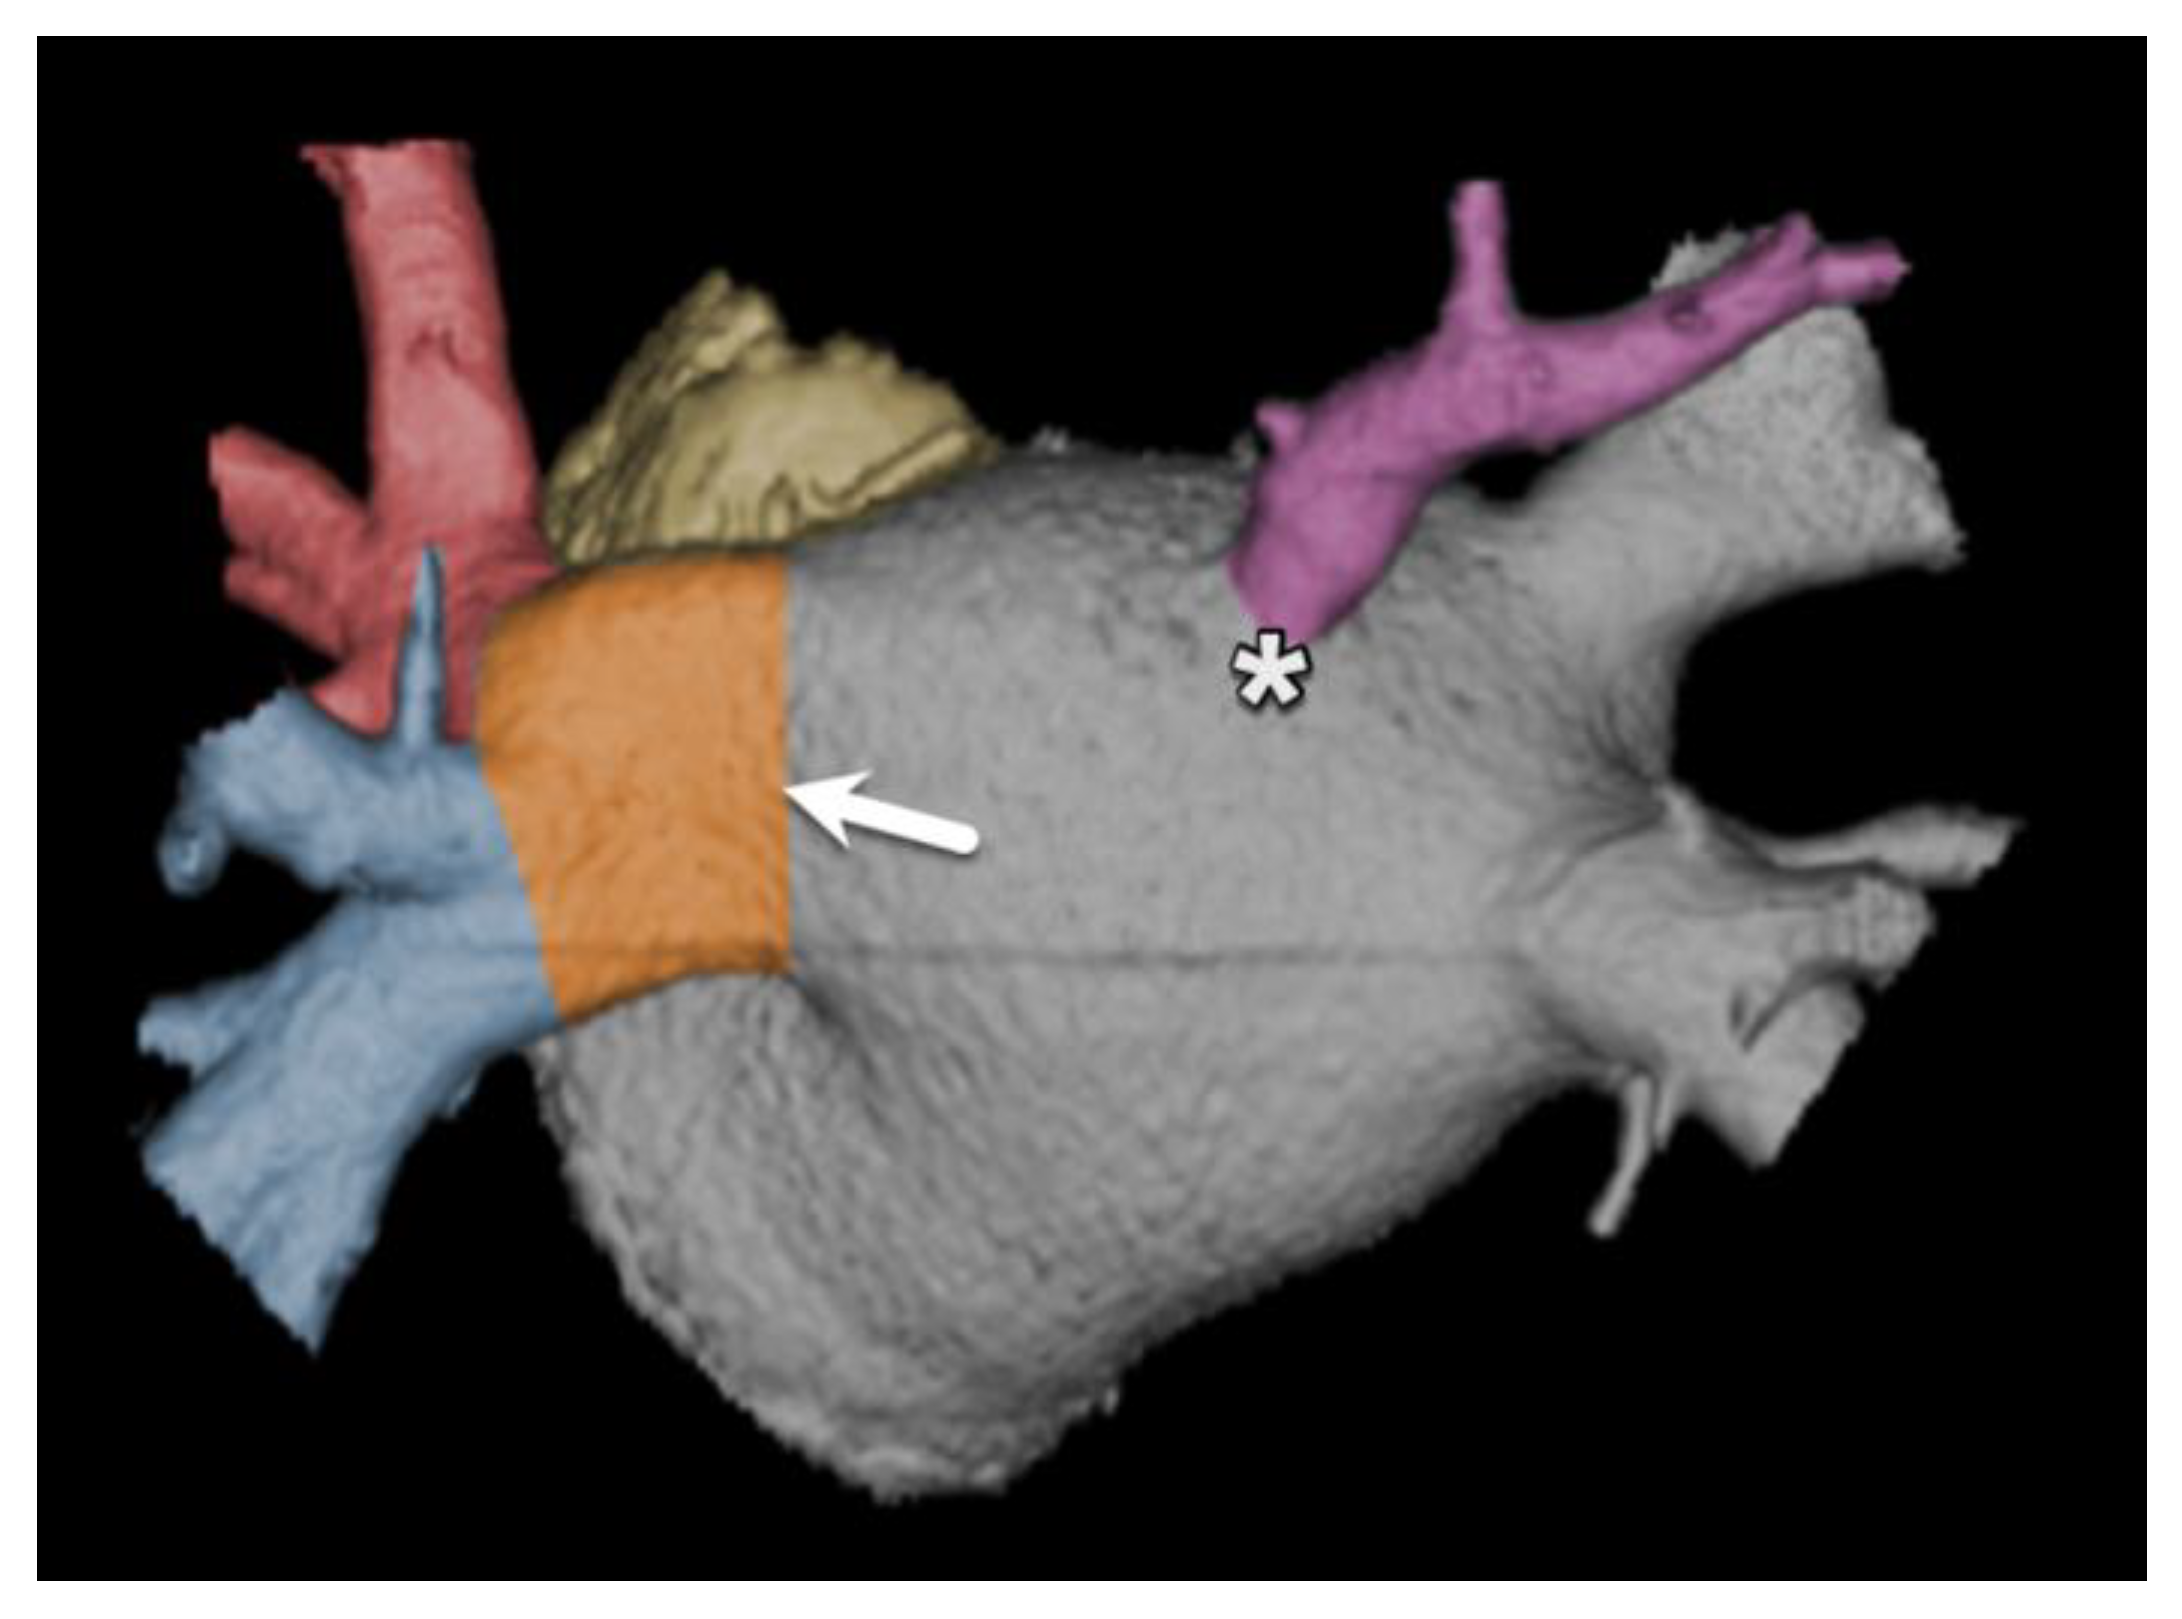

- Hell, M.M.; Emrich, T.; Kreidel, F.; Kreitner, K.-F.; Schoepf, U.J.; Münzel, T.; von Bardeleben, R.S. Computed tomography imaging needs for novel transcatheter tricuspid valve repair and replacement therapies. Eur. Heart J. Cardiovasc. Imaging 2020, 22, 601–610. [Google Scholar] [CrossRef] [PubMed]

- van Rosendael, P.J.; Kamperidis, V.; Kong, W.K.; van Rosendael, A.R.; van der Kley, F.; Ajmone Marsan, N.; Delgado, V.; Bax, J.J. Computed tomography for planning transcatheter tricuspid valve therapy. Eur. Heart J. 2017, 38, 665–674. [Google Scholar] [CrossRef] [PubMed]

- Faletra, F.F.; A Leo, L.; Paiocchi, V.L.; A Schlossbauer, S.; Borruso, M.G.; Pedrazzini, G.; Moccetti, T.; Ho, S.Y. Imaging-based tricuspid valve anatomy by computed tomography, magnetic resonance imaging, two and three-dimensional echocardiography: Correlation with anatomic specimen. Eur. Heart J. Cardiovasc. Imaging 2019, 20, 1–13. [Google Scholar] [CrossRef]